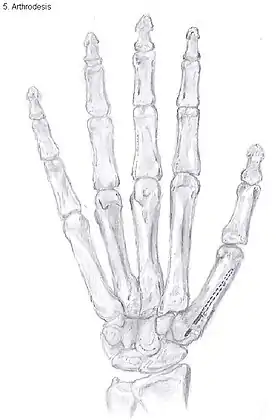

Arthrodesis

Arthrodesis of the TMC joint is a surgical procedure in which the trapezium bone and the metacarpal bone of the thumb are secured together. They are held together by K-wires or a plate and screws until the bone will heal.

Disadvantages include inability to flatten the hand.[27] Additionally, the stress on the CMC joint is now spread over the adjacent joints, those joints are more likely to develop osteoarthritis.[34]

Nevertheless, this procedure can be used in patients with stage II and III CMC OA as well as in young people with posttraumatic osteoarthritis.[27]